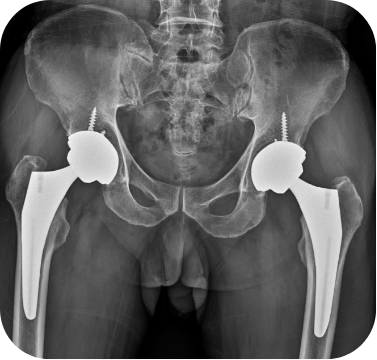

고관절 무혈성괴사 환자의 인공관절 전치환술 사례

• ▲ 수술 전

• ▲ 수술 후

고관절 퇴행성관절염 환자의 인공관절 전치환술 사례